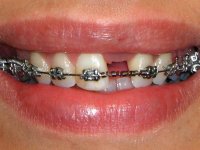

The orthodontic active treatment with straight wire technique (with high anchorage) lasts 14 months, followed by 6 months of contention with an acrylic removable prosthesis with a vestibular arch. The orthodontic treatment included a relatively rigid stabilizing wire and an open coil spring placed between the right central incisor and the left lateral incisor in order to obtain adequate space for the placement of an implant and crown in the left central incisor spot.